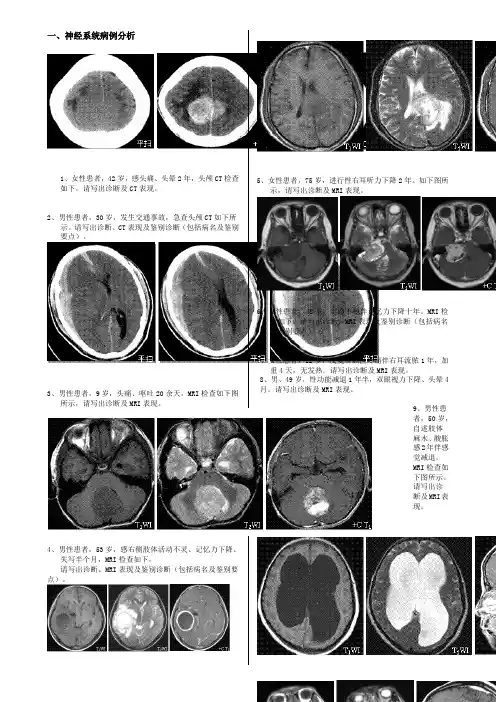

一、神经系统病例分析1、女性患者,42岁,感头痛、头晕2年,头颅CT检查如下。

请写出诊断及CT表现。

2、男性患者,30岁,发生交通事故,急查头颅CT如下所示。

请写出诊断、CT表现及鉴别诊断(包括病名及鉴别要点)。

3、男性患者,9岁,头痛、呕吐20余天,MRI检查如下图所示,请写出诊断及MRI表现。

4、男性患者,53岁,感右侧肢体活动不灵、记忆力下降、失写半个月,MRI检查如下,请写出诊断、MRI表现及鉴别诊断(包括病名及鉴别要点)。

5、女性患者,75岁,进行性右耳听力下降2年。

如下图所示,请写出诊断及MRI表现。